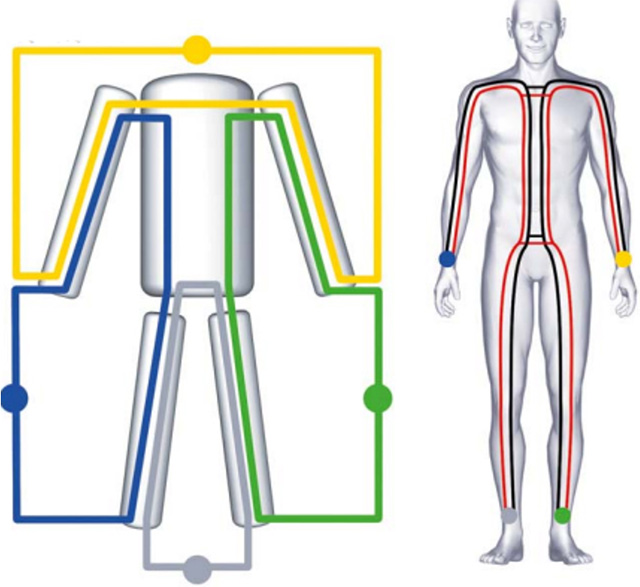

Beispiel einer Segment-Messung

Dargestellt werden die Segmente der beiden Extremitäten und der Rumpf. Die Fettmasse (FM) und die Fettfreie Masse (FFM) wurden gemessen.

Hier wird das Beispiel einer 10’000 Meter Läuferin gezeigt (59 Kg Körpergewicht). Anhand der Rohdaten Rz und Xc kann der unterschiedliche Trainingszustand der Körpersegmente erkannt werden.

Der Phasenwinkel der Beine ist mit 7.0 deutlich höher als derjenige der Arme mit 5.8, was bedeutet, dass die Beine mehr BCM enthalten.